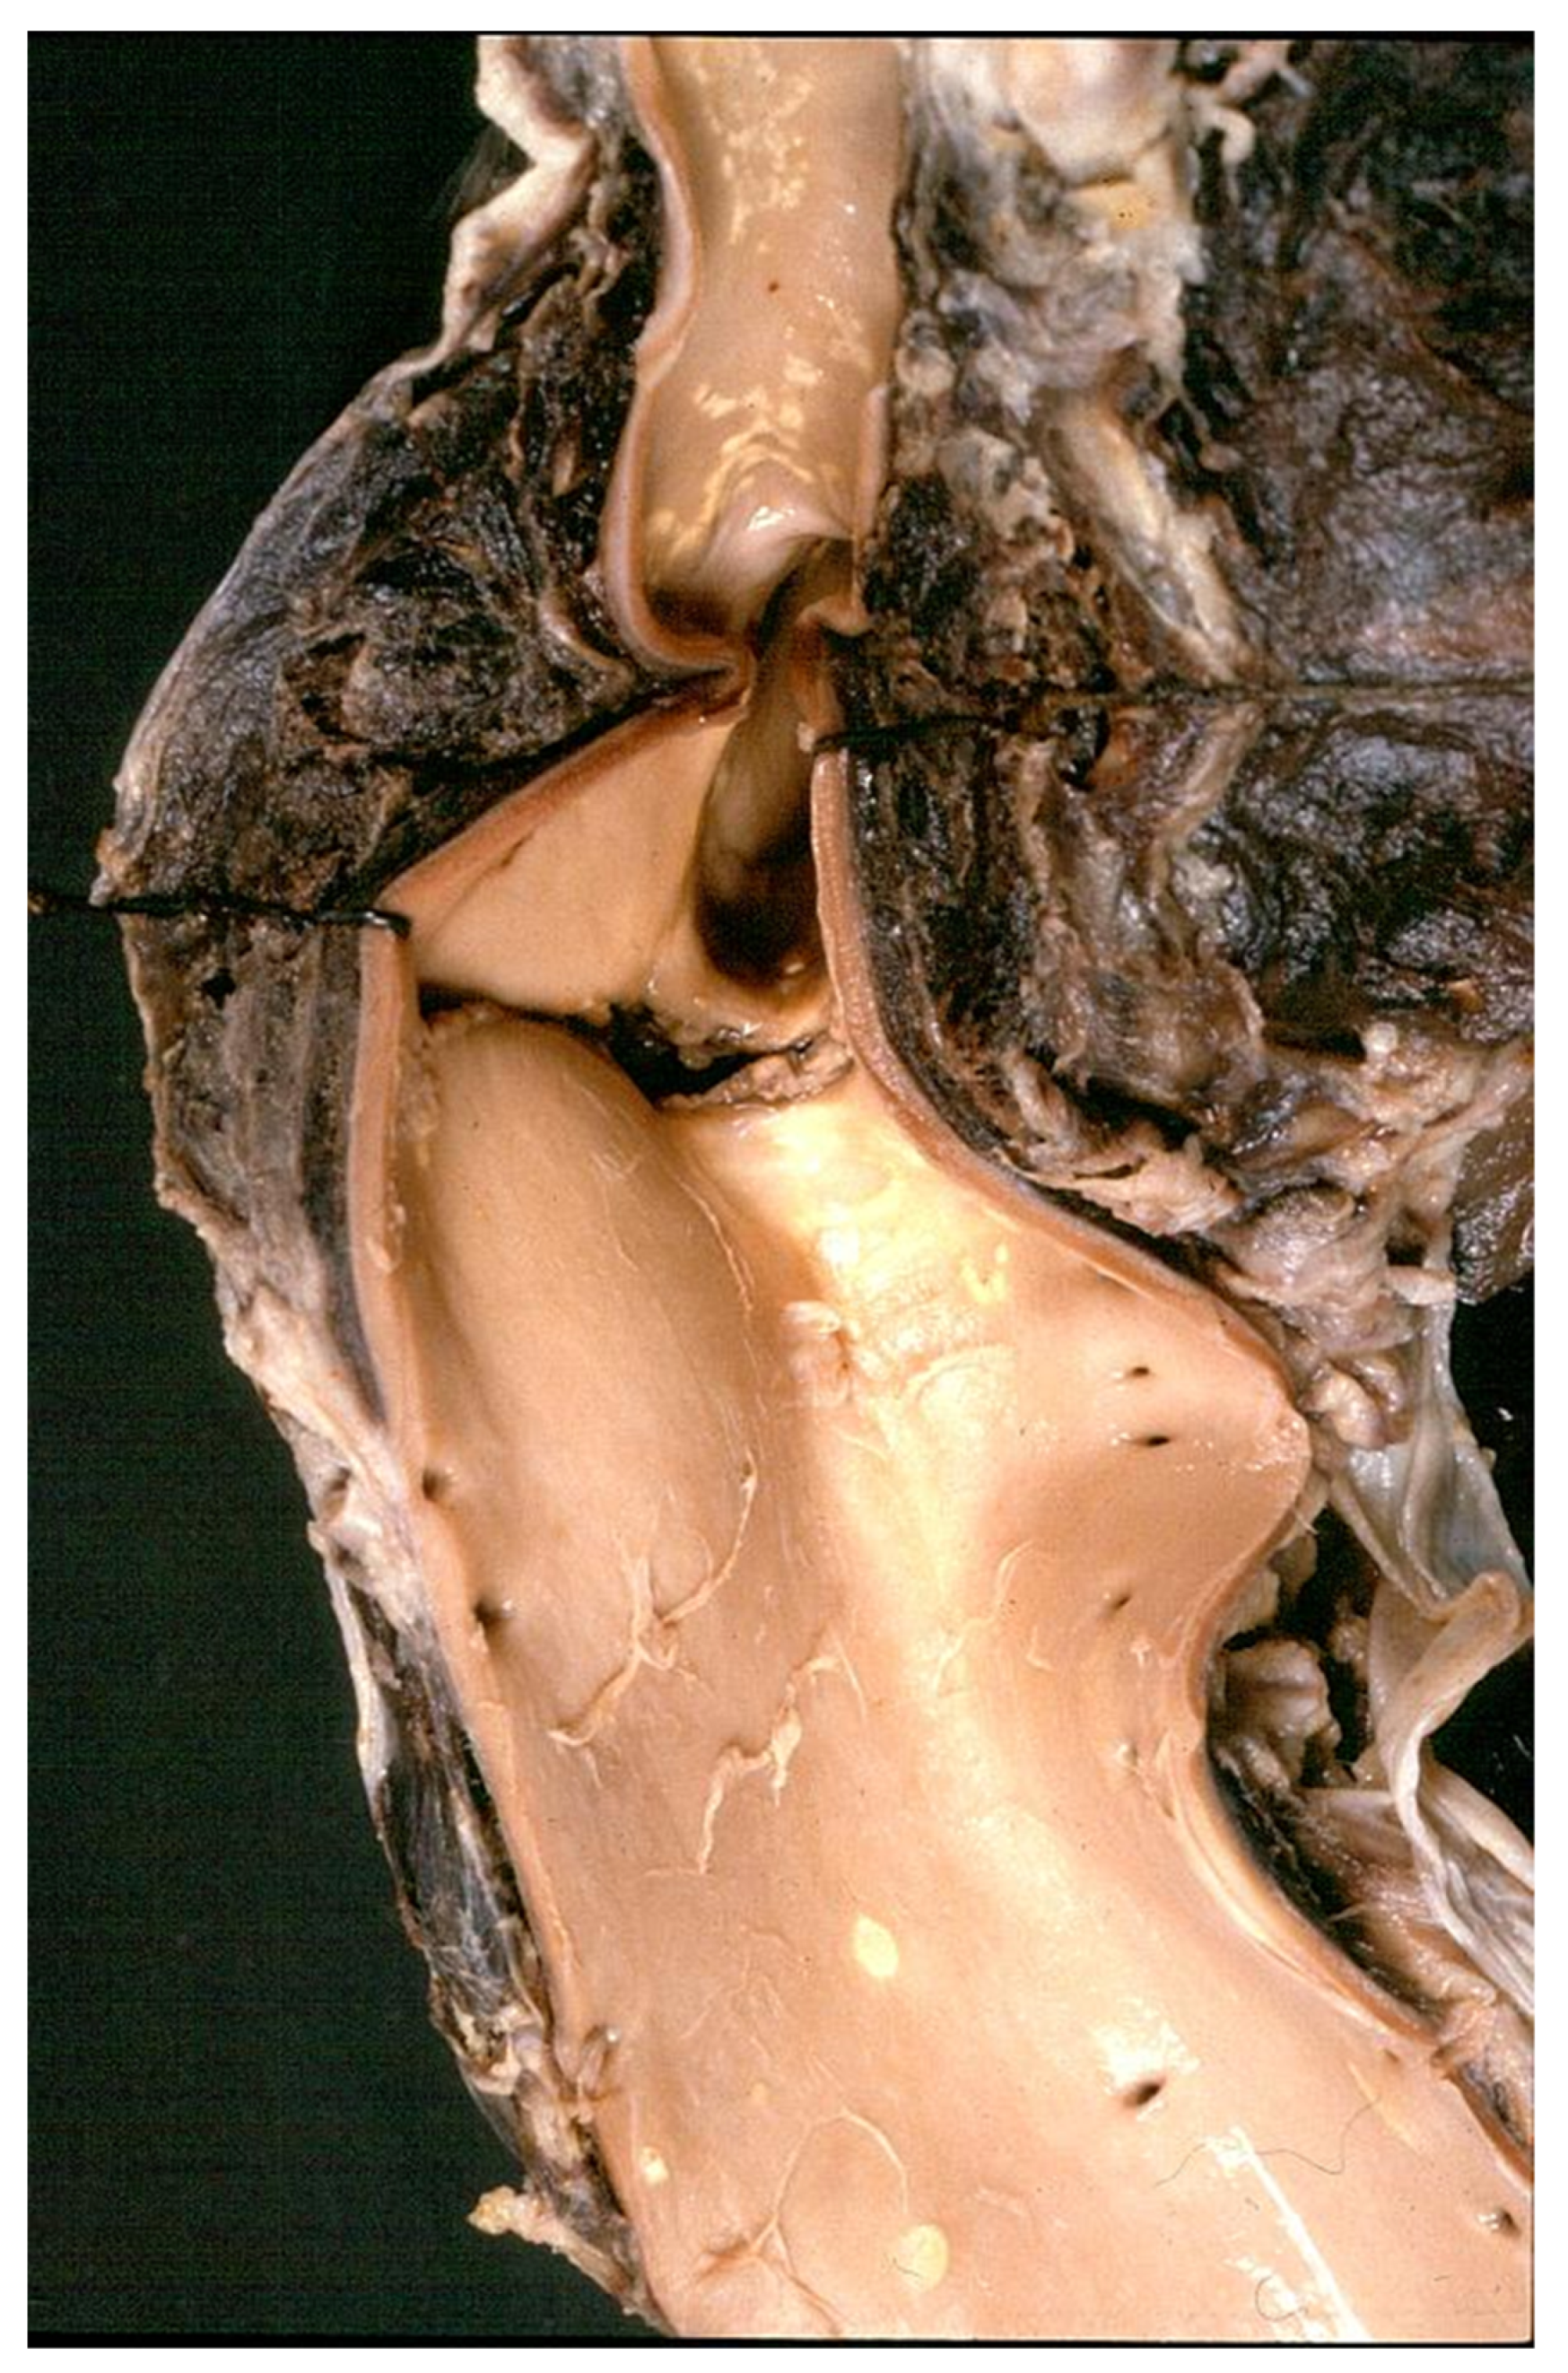

Classic aortic dissection starts from an intimal tear and proceeds forward (antegrade dissection) in the outer tunica media, with risk of external rupture, hemopericardium and cardiac tamponade in the case of the ascending aorta or left hemothorax in the case of the descending aorta. The dissection transforms the aorta into two lumens (true and false) and may involve vital arteries, such as carotid and renal, with organ ischemic injury. Reentry may occur with distal intimal tears, leading a double barrel chronic dissection of the aorta (Figure 21) [36]. Retrograde dissection towards the aortic root may be responsible for commissural dehiscence with aortic valve incompetence and coronary stems dissection with myocardial infarction. (Figure 22). Hemorrhagic infiltration of the aorto-atrial space and atrial septum may account for av block due to atrio-nodal discontinuity.

Figure 21. Double barrel aorta in chronic aortic dissection. (a) Gross view. (b) Corresponding histology. (Weigert Van Gieson stain).